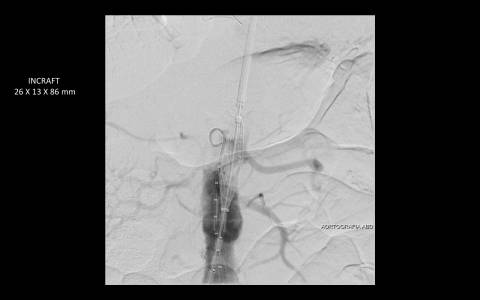

TRATAMENTO ENDOVASCULAR DE HEMATOMA INTRAMURAL DA AORTA ABDOMINAL COM ENDOPRÓTESE DE BAIXO PERFIL

Haja vista a extensa quantidade de comorbidades a cirurgia aberta se fazia de risco muito elevado para o paciente. Este foi então encaminhado para correção endovascular.

O estudo de angiotomografia evidenciou que as artérias iliacas externas e femorais apresentavam-se com muitas calcificações e ponto de estenose mais crítica em artéria ilíaca comum direita. Diante dos achados de imagem, foi optado por endoprotese de aorta abdominal de baixo perfil (Incraft – Cordis).